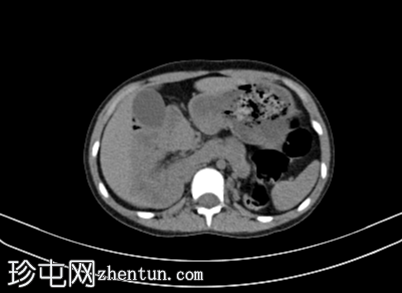

轴位

平扫

胰体和胰尾未显影,仅胰头显影,可能为背侧胰腺发育不全所致。

肠袢聚集于右侧肋下区,提示肠旋转不良。

左肾体积较小,肾实质相对扭曲,呈分叶状,可见少量肾实质囊肿。左肾上盏轻度突出。

右肾发育不全。

CT未见子宫/子宫发育不良;建议行MRI检查以作更佳评估。

左髂窝可见边界清晰的低密度影,右侧疑似存在类似结构,可能为异位卵巢。建议行MRI检查以进一步评估。

疑似肾下段下腔静脉(IVC)缺如。

轻度耻骨联合分离。